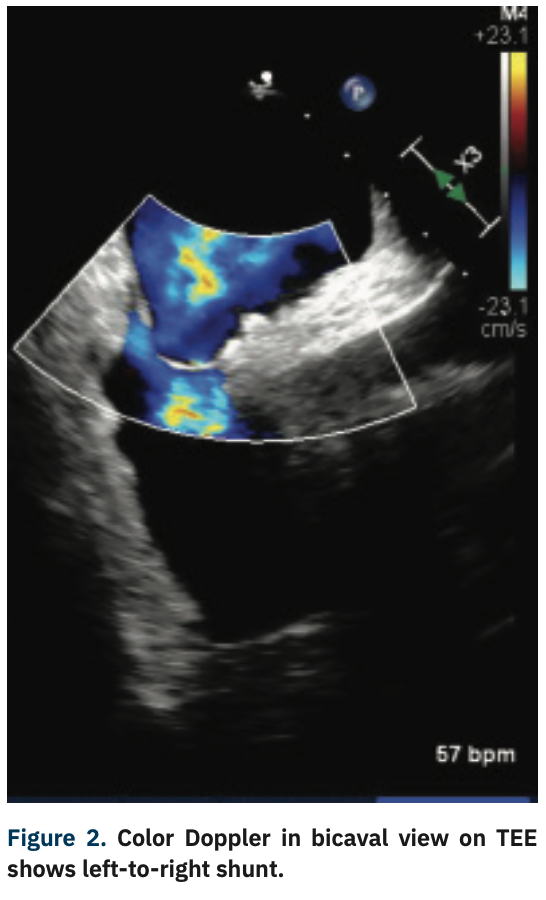

Given the degree of right-to-left shunting with agitated saline at baseline, there was a high index of suspicion for Platypnea-orthodeoxia syndrome. Repeat echocardiography with agitated saline in both supine and upright position was performed and demonstrated a profound right-to-left shunt within one cardiac cycle in the upright position (Figures 3-4).